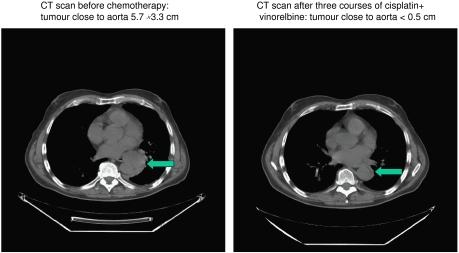

The aim was to evaluate the activity of cisplatin and vinorelbine in previously untreated, inoperable patients having histologically verified malignant pleural mesothelioma (MPM), normal organ function, and performance status 0-2. Treatment was vinorelbine 25 mg m(-2) i.v. weekly and cisplatin 100 mg m(-2) i.v. every 4 weeks with hydration and standard prophylactic antiemetic treatment. Patients gave written informed consent. Characteristics of 54 consecutive patients were: males 85%, epithelial subtype 74%, IMIG stages III and IV 35 and 46%, performance status 0, 1, and 2, 26, 69, and 6%, and median age 63 years (31-78 years). CTC grade 3 or 4 toxicity occurred with respect to leukocytopenia (48% of patients, grade 4 in 13%), nausea (13%), neurotoxicity (11%), nephrotoxicity (4%), and other toxicities (9%). There were no toxic deaths. The median number of cycles was four. The fraction of patients alive at 1-, 2-, and 3-years were 61, 31, and 4%, respectively, and median survival and median time to progression were 16.8 months (0.5 to 46.4 +months) and 7.2 months (1.6 to 40.6 + months). There were two CRs and 14 PRs (response rate 29.6%). Cisplatin and intravenous vinorelbine is a highly active regimen in MPM with a response rate and survival comparable to the most active regimens so far reported.